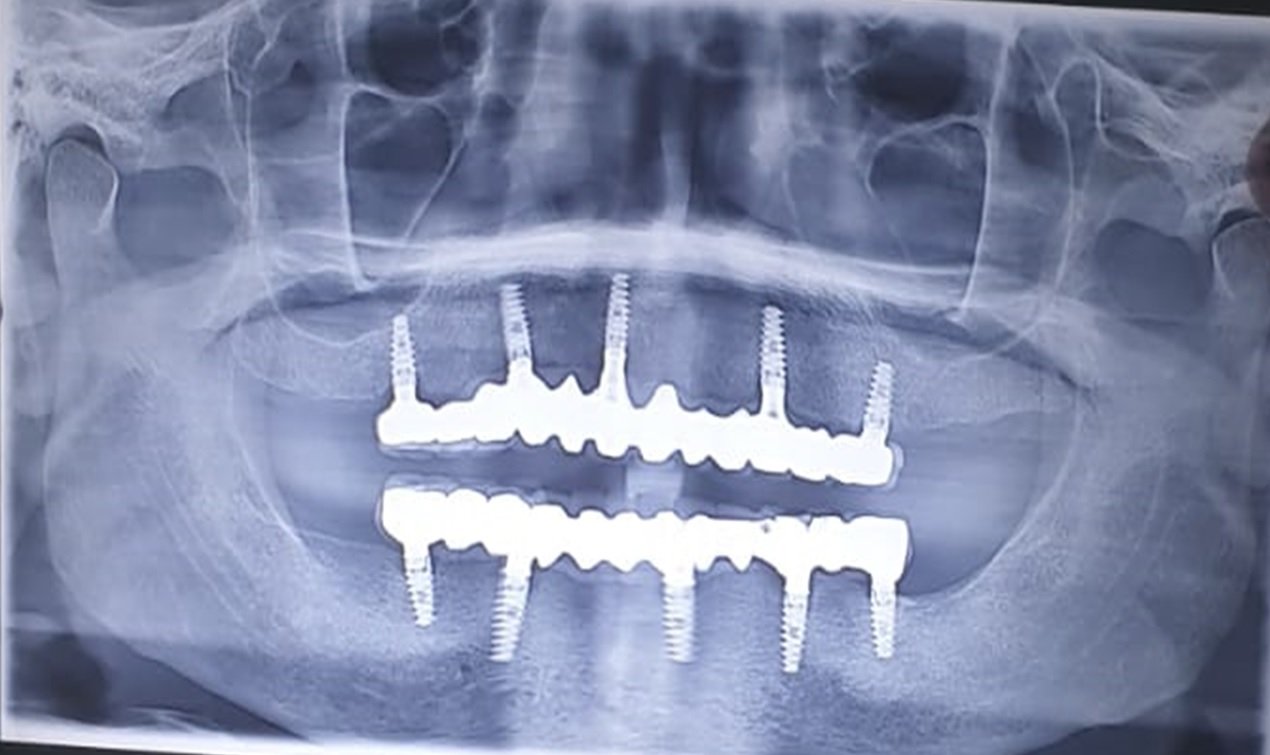

The OPG( Fig .3) was taken to evaluate the condition of the teeth that were present and the condition of the bone for implants. Patient was well informed and explained about the various treatment options like removable and implant supported fixed prostheses.

Fig .3: PREOPERATIVE INTRAORAL RADIOGRAPH

In the current case report, fixed full-arch implant rehabilitation was selected for the definitive prosthetic design of the maxillary and mandibular arch. The distribution of implants was followed according to the prosthodontic plan. The maxillary and mandibular arch included a five-unit implant supported PFM.